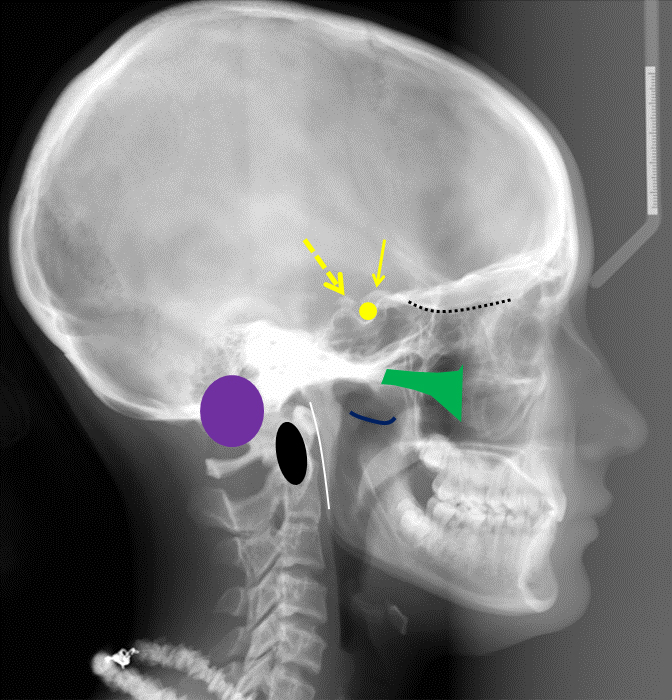

КТ анатомия сосцевидного отростка: особенности и показания

Раздел: Галерея прозрений